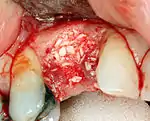

Placing the implant

Most implant systems have five basic steps for placement of each implant:[15]: 214–221

- Soft tissue reflection: An incision is made over the crest of bone, splitting the thicker attached gingiva roughly in half so that the final implant will have a thick band of tissue around it. The edges of tissue, each referred to as a flap are pushed back to expose the bone. Flapless surgery is an alternate technique, where a small punch of tissue (the diameter of the implant) is removed for implant placement rather than raising flaps.

- Drilling at high speed: After reflecting the soft tissue, and using a surgical guide or stent as necessary, pilot holes are placed with precision drills at highly regulated speed to prevent burning or pressure necrosis of the bone.

- Drilling at low speed: The pilot hole is expanded by using progressively wider drills (typically between three and seven successive drilling steps, depending on implant width and length). Care is taken not to damage the osteoblast or bone cells by overheating. A cooling saline or water spray keeps the temperature low.

- Placement of the implant: The implant screw is placed and can be self-tapping,[32]: 100–102 otherwise the prepared site is tapped with an implant analog. It is then screwed into place with a torque controlled wrench[36] at a precise torque so as not to overload the surrounding bone (overloaded bone can die, a condition called osteonecrosis, which may lead to failure of the implant to fully integrate or bond with the jawbone).

- Tissue adaptation: The gingiva is adapted around the entire implant to provide a thick band of healthy tissue around the healing abutment. In contrast, an implant can be "buried", where the top of the implant is sealed with a cover screw and the tissue is closed to completely cover it. A second procedure would then be required to uncover the implant at a later date.

Additional procedures to augment deficient bone in implant site

For an implant to osseointegrate, it needs to be surrounded by a healthy quantity of bone. In order for it to survive long-term, it needs to have a thick healthy soft tissue (gingiva) envelope around it. It is common for either the bone or soft tissue to be so deficient that the surgeon needs to reconstruct it either before or during implant placement.[32]: 1084

Hard tissue (bone) reconstruction

Bone grafting is necessary when there is a lack of bone. Also, it helps to stabilize the implant by increasing survival of the implant and decreasing marginal bone level loss.[41] While there are always new implant types, such as short implants, and techniques to allow compromise, a general treatment goal is to have a minimum of 10 mm (0.39 in) in bone height, and 6 mm (0.24 in) in width. Alternatively, bone defects are graded from A to D (A=10+ mm of bone, B=7–9 mm, C=4–6 mm and D=0–3 mm) where an implant's likelihood of osseointegrating is related to the grade of bone.[42]: 250

To achieve an adequate width and height of bone, various bone grafting techniques have been developed. The most frequently used is called guided bone graft augmentation where a defect is filled with either natural (harvested or autograft) bone or allograft (donor bone or synthetic bone substitute), covered with a semi-permeable membrane and allowed to heal. During the healing phase, natural bone replaces the graft forming a new bony base for the implant.[38]: 223